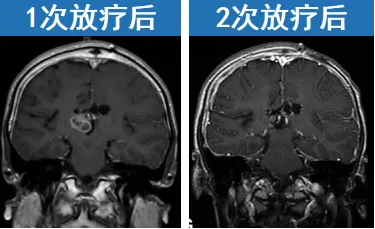

手术只是治疗的基础,为控制肿瘤进展,鲁特卡教授为肖恩制定了一套局部放疗方案。在经历2次放疗后,随访显示肖恩的病情得到控制,并已安全成长6年,期间没有复发,而肖恩也顺利步入成年。